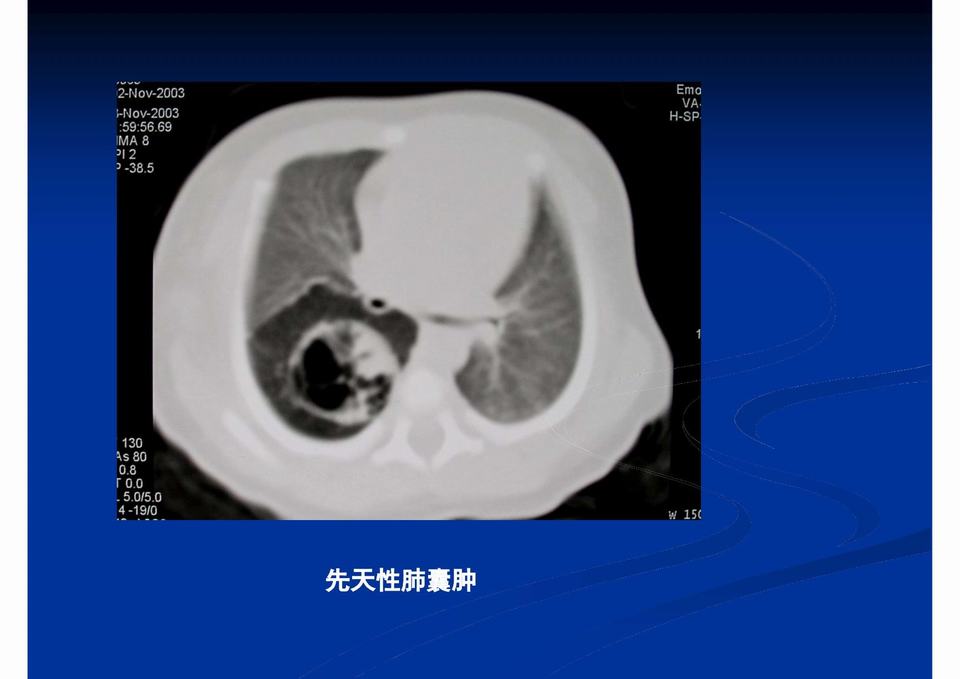

【PPT】儿童胸部影像学